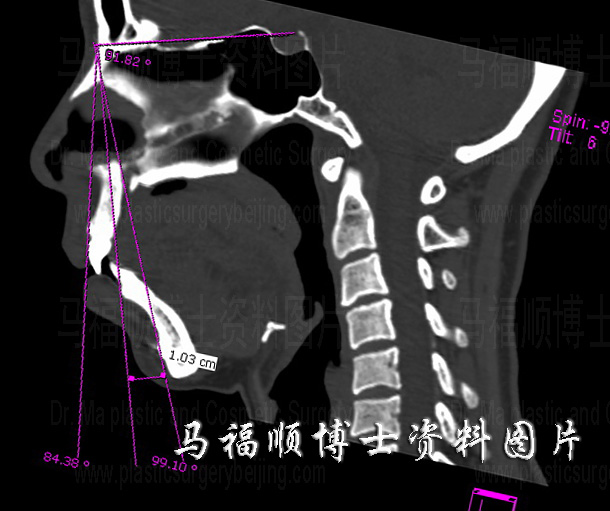

矢状切面CT片中可见上下颌骨前突,与后缩的下颏形成明显的角度差。

前文已经叙述这位美女分次做了三项手术,第一次手术是双颌前突整形术,是改变她外观最大的手术。这是因为她术前上下颌及牙齿明显地向前突出超出了正常范围,如右侧CT片所示。致使她的面部轮廓线条不美观,也可以说这是她面部的最大问题。这一问题一旦矫正她的容貌就有很大的提升。从术前的照片及CT片上都可以看出美女术前不只是单纯的双颌前突,同时还伴有明显的下颏后缩,造成SNA角与SAD角的差值高达15度。虽然在下颌后推时采用了“H”截骨旋转后推法,在后推牙齿的同时让下巴向前移动,但下颏的前移程度仍不能满足正常外观的要求。所以二期还需水平截骨颏前移整形术,有人也叫做下巴前移或前拉术,使下颏点向前移动了1CM,才达后术后照片中的效果。

对于适应人群来说,双颌前突整形术不失为一收益与付出比很高的手术。正确的选择手术方式和操作,特别是正确地计算上下颌骨后推的距离对于取得好的手术效果至关重要。后推不足不能完全改善容貌,后推过度又会造成双颌后缩,使人显得苍老。好在通过CT成像技术可以很精确地测量突出的程度,并能使手术大夫很好地了解上下颌骨之间及其与面部其它骨骼之间对应关系。比传统的利用手术中目测判断后推量的方法更精确,同时手术时间也明显缩短。